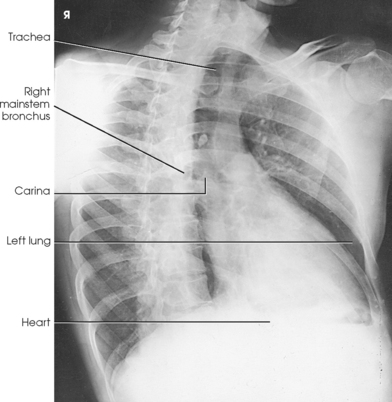

LAO position: The maximum area of the right lung field (side farther from the IR) is shown along with the thoracic viscera. The anterior portion of the left lung is superimposed by the spine (Figs. 10-43 and 10-44). Also shown are the trachea and its bifurcation (the carina) and the entire right branch of the bronchial tree. The heart, the descending aorta (lying just in front of the spinae), and the arch of the aorta are also presented.

RAO position: The maximum area of the left lung field (side farther from the IR) is shown along with the thoracic viscera. The anterior portion of the right lung is superimposed by the spine (Figs. 10-45 and 10-46). Also shown are the trachea and the entire left branch of the bronchial tree. This position gives the best image of the left atrium, the anterior portion of the apex of the left ventricle, and the right retrocardiac space. When filled with barium, the esophagus is shown clearly in the RAO and LAO positions (see Fig. 10-46).